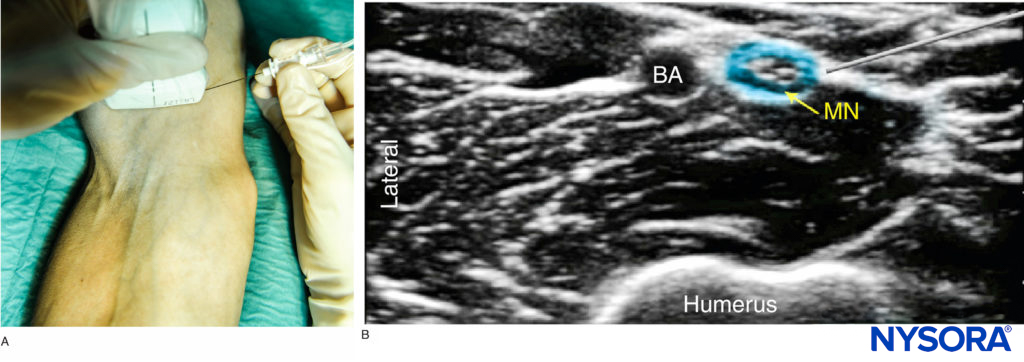

The median nerve is imaged at the level of the elbow crease, as it is located superficially. The transducer is placed just above the crease and adjusted to obtain a clear view of the brachial artery. The median nerve lies on the medial side in close contact to the artery as a hyperechoic oval-shaped structure of about the same size of the artery (Figure 4). Scanning proximally, both the nerve and the artery can be easily followed up to the axilla as they course together, although changing the relative position to one another. Scanning distally to the elbow crease, the median nerve separates from the artery and lies deep to the pronator teres muscle and the flexor digitorum superficialis as it reaches the mid-forearm.

FIGURE 4 (A) Anatomy section of the distal arm at the level of the elbow. (B) Sonoanatomy of the median nerve proximally to the elbow crease.

The Median Nerve

With the arm abducted and the palm facing up, the skin of the anterior and medial side of the elbow is disinfected and the transducer positioned transversely on the antecubital fossa. The median nerve should be identified on the medial side of the artery. If it is not immediately visualized, the transducer should be positioned slightly more medially and the brachial artery identified using color Doppler ultrasound. The needle is inserted in-plane from either side of the transducer, although a medial to lateral approach is usually more convenient to avoid the artery that lies lateral to the nerve. (Figure 7a). After negative aspiration, 4–5 mL of local anesthetic is injected (Figure 7b). If the spread is inadequate, slight adjustments can be made and a further 2–3 mL of local anesthetic administered.